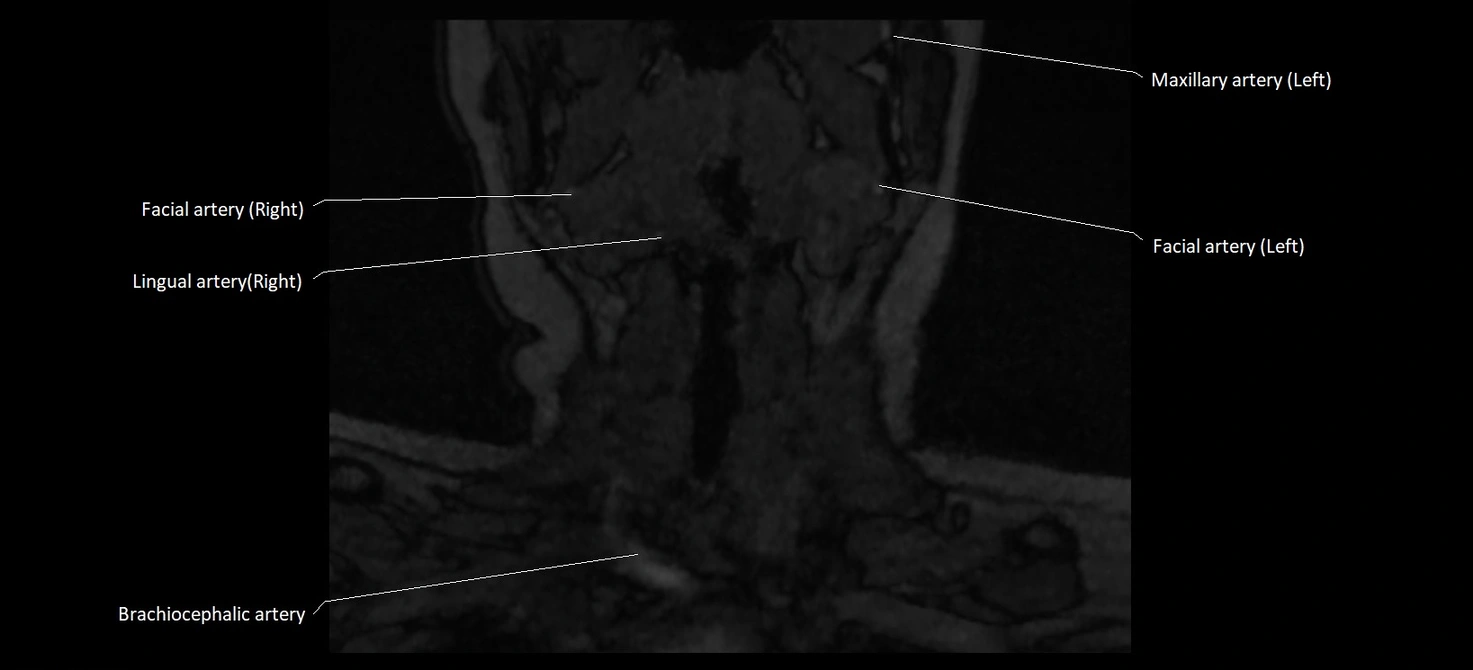

MRI images

image